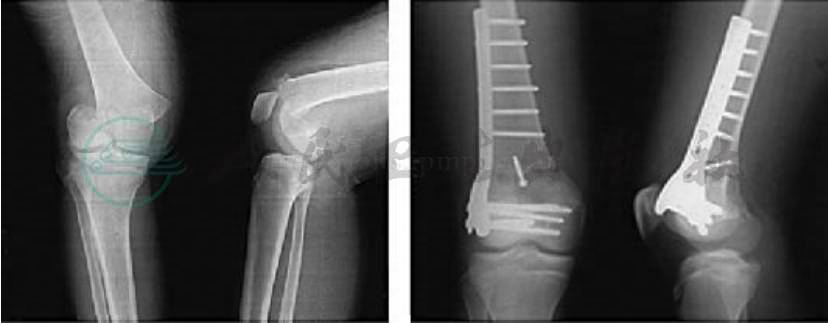

股骨髁上骨折大多病例为高速或由高处坠落损伤所致。老年患者因干骺端骨质疏松,屈膝位跌倒即可引起髁上的嵌入骨折。骨折常呈典型移位,远骨折块由于四头肌,腘绳肌及腓肠肌的牵拉短缩并向后移位和成角,内收肌的作用使股骨远端内翻内旋(图1)。由于骨折远骨折端向后移位偶可导致腘动脉损伤,局部可见张力性肿胀,小腿表现有缺血征象,治疗前若未注意常可引起不良后果。摄X线片可确定诊断,了解骨折的类型和移位情况有助于对创伤病理的分析。X线片应包括整个股骨干和髋关节,以免漏诊股骨颈骨折和髋脱位,偶尔需摄其他方位X线片和CT来确定骨折是否波及关节内。

图1 股骨髁上骨折的典型移位

股骨髁上骨折通常以骨折类型分类,骨折线虽可累及股骨髁或髁间部位,但主要骨折仍是在股骨髁上部位,以髁部为主的骨折,将在股骨髁骨折中讨论。髁上骨折因受伤机制不同,可分为无移位、嵌入、移位或粉碎的几种类型。多见横断或斜形的移位骨折,粉碎性的较少(图2)。开放骨折股骨近端常在髌上部位穿出大腿皮肤。